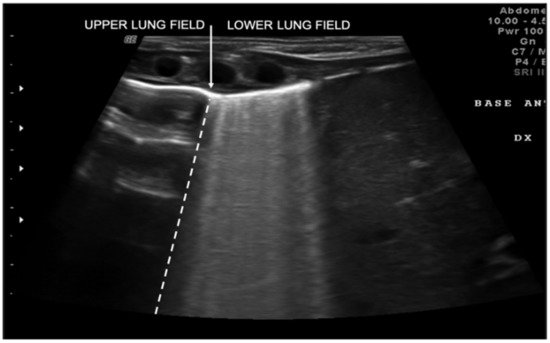

Transient tachypnea of the newborn (TTN), also known as “wet lung,” is caused by a failure in the reabsorption of fluid from the fetal lung. It is typical of term or post-term infants in the case of rapid delivery or cesarean section [17]. Infants with TTN present compact B-lines in the lower lung fields and fewer and less compact B-lines in the upper fields in one or both lungs. These signs, also known as double-lung points, appear because of the greater involvement of the lower lung fields in the disease and are characterized by a sharp ultrasound demarcation line between the upper and lower lung fields of both lungs (Figure 5) [10]. The pleural line is regular, with normal echogenicity and movement with respiratory acts. In contrast to NRDS, no subpleural consolidations are observed. Due to these typical ultrasonographic findings, much evidence has shown how pulmonary ultrasonography can be useful in the early diagnosis of TTN and differentiate TTN from NRDS already by the first hours of life [18].

Figure 5. Transient tachypnea of the newborn. The dashed line shows the ultrasound demarcation line between the upper and lower lung fields: double-lung point (white arrow).